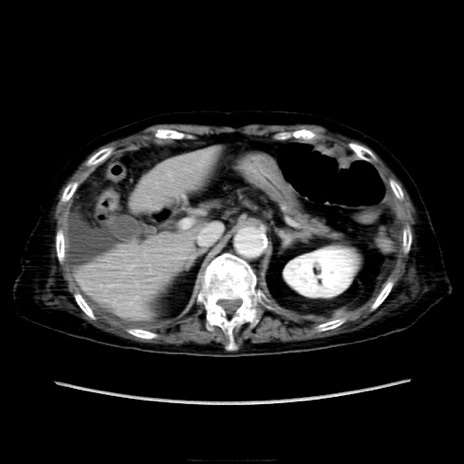

症例40(横断像)

【症例】90歳代女性

【主訴】腹痛・嘔吐

【現病歴】 食欲低下、嘔吐があり昨日他院受診。肺炎と診断され入院となる。入院後より腹部全体に圧痛あり。胃管留置され経過みていたが、症状持続するため、

当院転院となる。

【既往歴】胸椎圧迫骨折、胆石症

【身体所見】腹部:中央に激痛あり、圧痛あり、反跳痛不明

【データ】WBC 17100、CRP 18.82